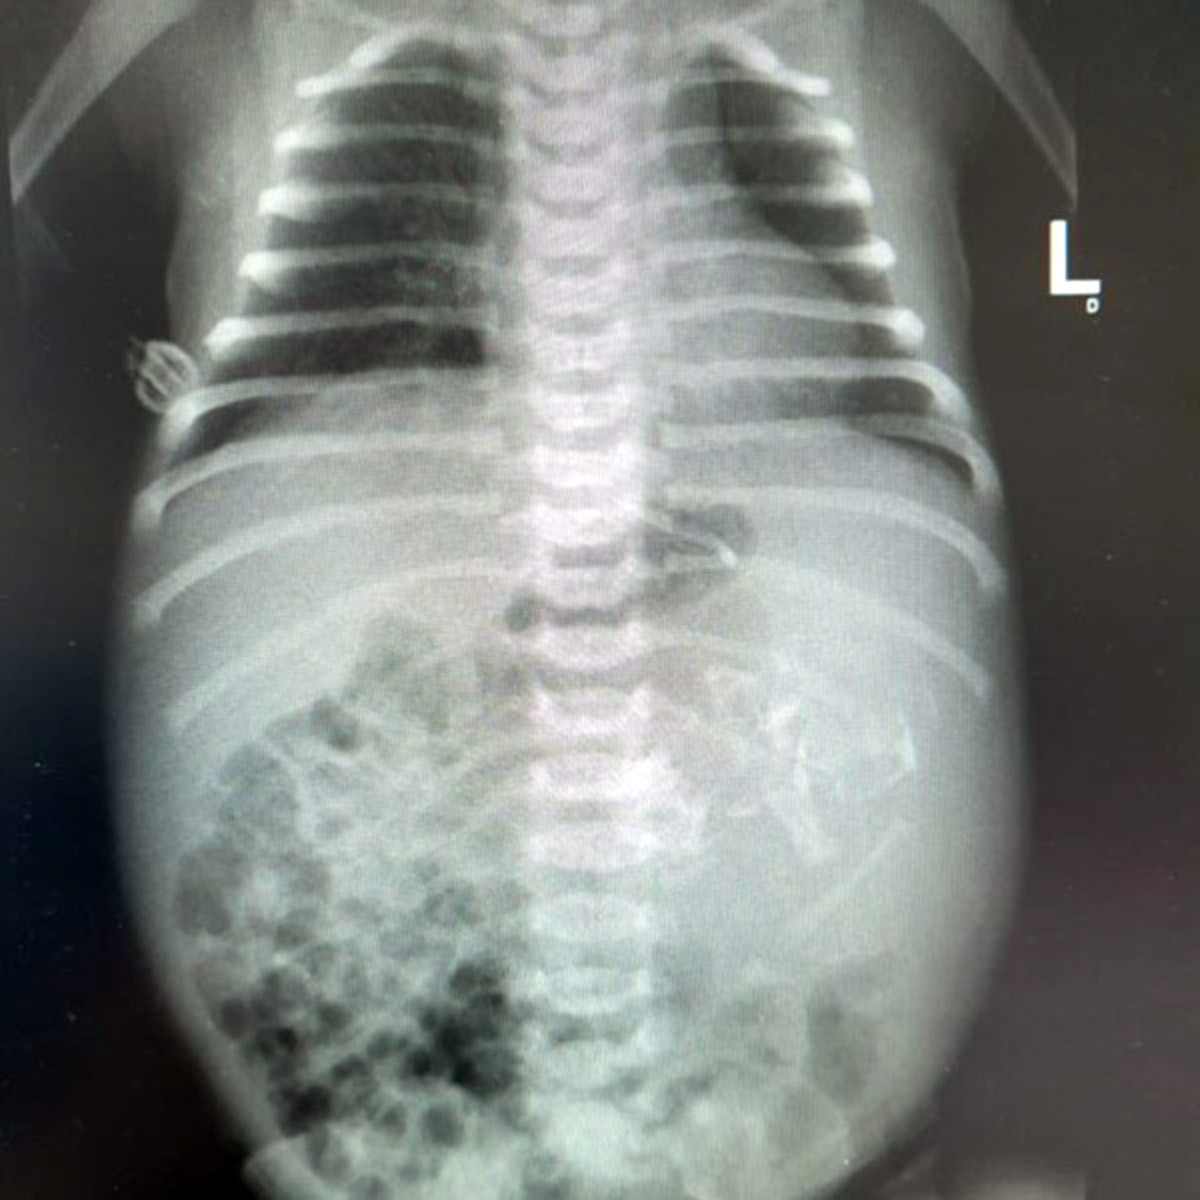

डॉक्टरों को इस बात का शक तब हुआ जब उन्होंने नवजात का पेट अन्य बच्चों की तुलना में ज्यादा बड़ा पाया. इसके बाद नवजात का अल्ट्रासाउंड और एक्स-रे किया गया.

(फोटो- Assuta Hospital)

जिसमें पता चला कि बच्ची के पेट में एक भ्रूण विकसित हो रहा है. जो कि पिछले 10 हफ्तों से विकसित हो रहा था. इस दौरान भ्रूण का दिल, हाथ और पैर विकसित हो रहे थे.

(फोटो- गेटी)